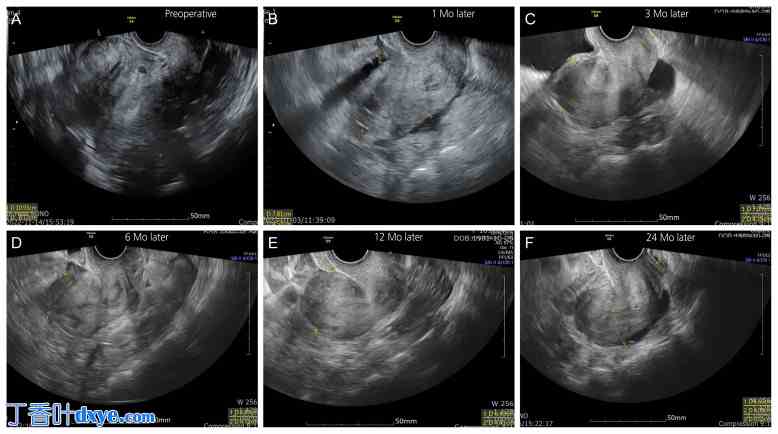

即使在子宫底切除术后的超声检查中,子宫形态也保持良好,月经量和痛经等症状均有所减轻。在2年的随访期内,未观察到子宫增大或临床症状恶化的病例,也未发现其他与手术相关的并发症(图4)。在24个月的随访期内,所有患者均未出现子宫增大或进行性增大。少数患者出现子宫肌瘤或子宫腺肌症复发;然而,术后2年内无患者需要再次手术。术中,子宫底切除组和子宫肌瘤切除组在技术上未观察到显著差异。然而,子宫底切除术后,子宫底壁可能仍然相对较薄。因此,在后续的宫内操作(如刮宫术或宫腔镜检查)中,子宫穿孔的风险显著增加,临床实践中应予以充分考虑。

图 4.

4.jpg

单孔腹腔镜下子宫底切除术后患者的子宫超声图像。(A) 术前,(B) 术后 1 个月,(C) 术后 3 个月,(D) 术后 6 个月,(E) 术后 12 个月,(F) 术后 24 个月。Mo,月。